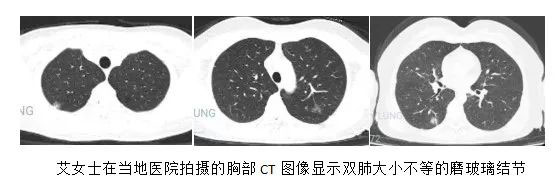

李某的母亲艾女士素来身体健康,但就在今年2月中旬出现了咳嗽、胸闷、深呼吸时胸口发痒、后背疼的症状,吓得她赶紧在当地医院拍了胸部CT,然而诊断结果却让全家陷入了恐慌之中。CT图像显示双肺多发磨玻璃结节,最大的结节直径约2厘米,诊断为双肺多发恶性病变可能。

李某觉得丈夫的话很有道理,于是抱着最后一丝希望,来到了首都医科大学附属北京胸科医院影像专家门诊。侯代伦教授严肃认真地看了好一会儿艾女士的胸部CT片,多年的临床实践和潜心钻研,让他练就了一双火眼金睛,在了解了大致病史后他微笑着说:“你这不是肺癌,但长的太像肺癌了,双肺多发的磨玻璃结节边界都很模糊,这要么是特殊感染,要么是过敏,先消炎看看,或者做个气管镜刷检取证,建议入院完善相关检查。”侯主任自信的话语给了艾女士一家新的希望,当即决定要在北京胸科医院进行进一步检查及治疗。经过我院呼吸科半个月的抗炎治疗后,艾女士肺内的磨玻璃结节体积越来越小,密度越来越淡,艾女士精神状态明显好转,经医生评估可出院休养,艾女士回到了老家哈尔滨休息,等待病灶的继续吸收。